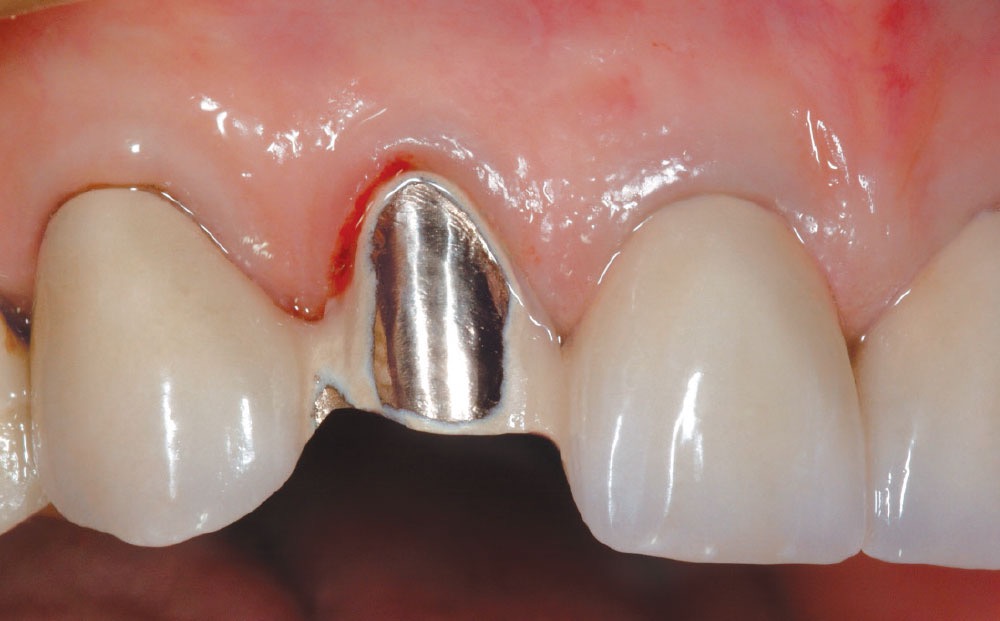

✔ 1️⃣ 利用「植牙牙橋」

例如缺 3 顆牙,不一定要 3 顆植體,

可以用 2 顆植體支撐 3 顆牙橋,安全又省,但前提是咬合力要輕、清潔要能徹底、無牙周疾病…等,始適用!(通常用於前牙)

✔ 2️⃣ 前牙區(美觀區)

前牙力量很小,有時部分植體做成植牙牙橋即可處理。前提是後牙區兩側均有穩定咬合,可輪流咀嚼!